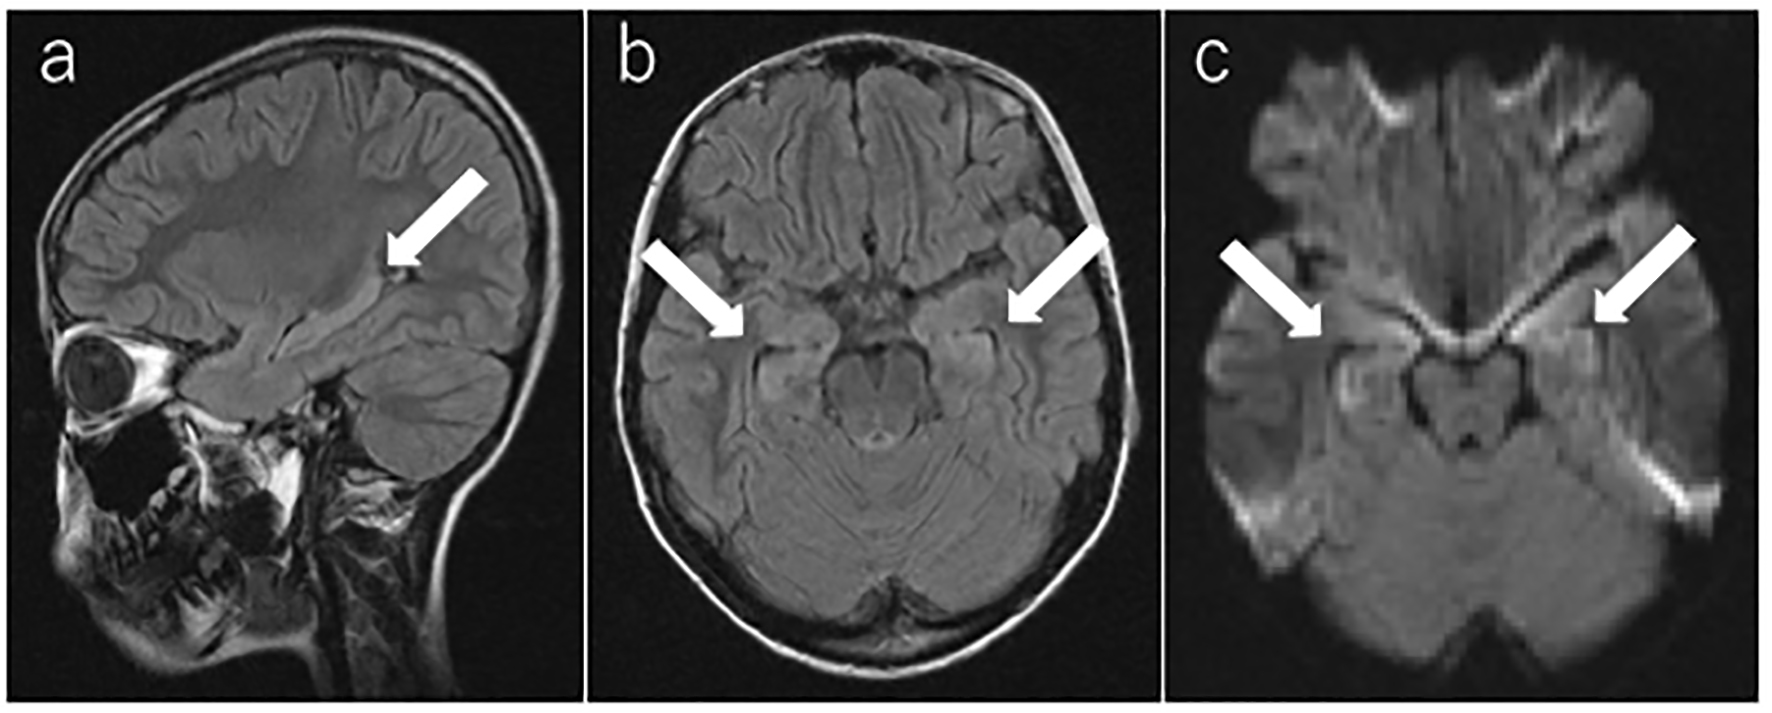

Laboratory blood test results were normal, including a full blood count, serum electrolytes, total protein, albumin, blood urea nitrogen, creatinine, aspartate aminotransferase, alanine aminotransferase, lactate dehydrogenase, alkaline phosphatase, creatine kinase, glucose, C-reactive protein, and anti-nuclear antibody. Her cerebrospinal fluid (CSF) showed lymphocytic pleocytosis of 16 nucleated cells/mm3 with 100% lymphocytes and normal glucose and protein levels. Myelin basic protein and oligoclonal bands of immunoglobulin G in the CSF were negative. Herpes simplex virus DNA was not detected by real time PCR. Bacterial infection was not suspicious; therefore, cultivation of the CSF was not performed. Electroencephalography (EEG) showed generalized slow waves and no definitive epileptic discharges. Brain MRI was performed on the second day of admission (day 14). T2-weighted fluid-attenuated inversion recovery (FLAIR) and diffusion-weighted images showed hyperintense lesions in the bilateral medial temporal lobes and hippocampus (Fig. 1).

Figure 1.

Click for large image

Figure 1. Brain magnetic resonance imaging. (a, b) T2-weighted fluid-attenuated inversion recovery image and (c) diffusion-weighted image on the second day of admission (day 14). The arrow shows the high-intensity areas in the bilateral medial temporal lobes and hippocampus.

Brain MRI findings are abnormal in 33-50% of affected patients [1, 2]. On T2-weighted or FLAIR MRI, signal hyperintensity might be seen in the hippocampi, cerebellar or cerebral cortex, frontobasal and insular regions, basal ganglia, brain stem, and, infrequently, the spinal cord. These findings are usually mild or transient and can be accompanied by subtle contrast enhancement in the affected areas or meninges [7]. In the present case, T2-weighted FLAIR imaging and diffusion-weighted imaging on the second day of admission (day 14) showed high-intensity areas in the bilateral medial temporal lobes and hippocampus.